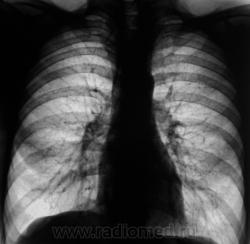

Еще контроль через 1 месяц.

Распад был изначально, но, к счастью больного, все закончилось практическим выздоровлением.

Долго что-то пневмонию лечили. А распад очень сомнительный. Больше на игру теней похож.

Да, лечение весьма затянулось.